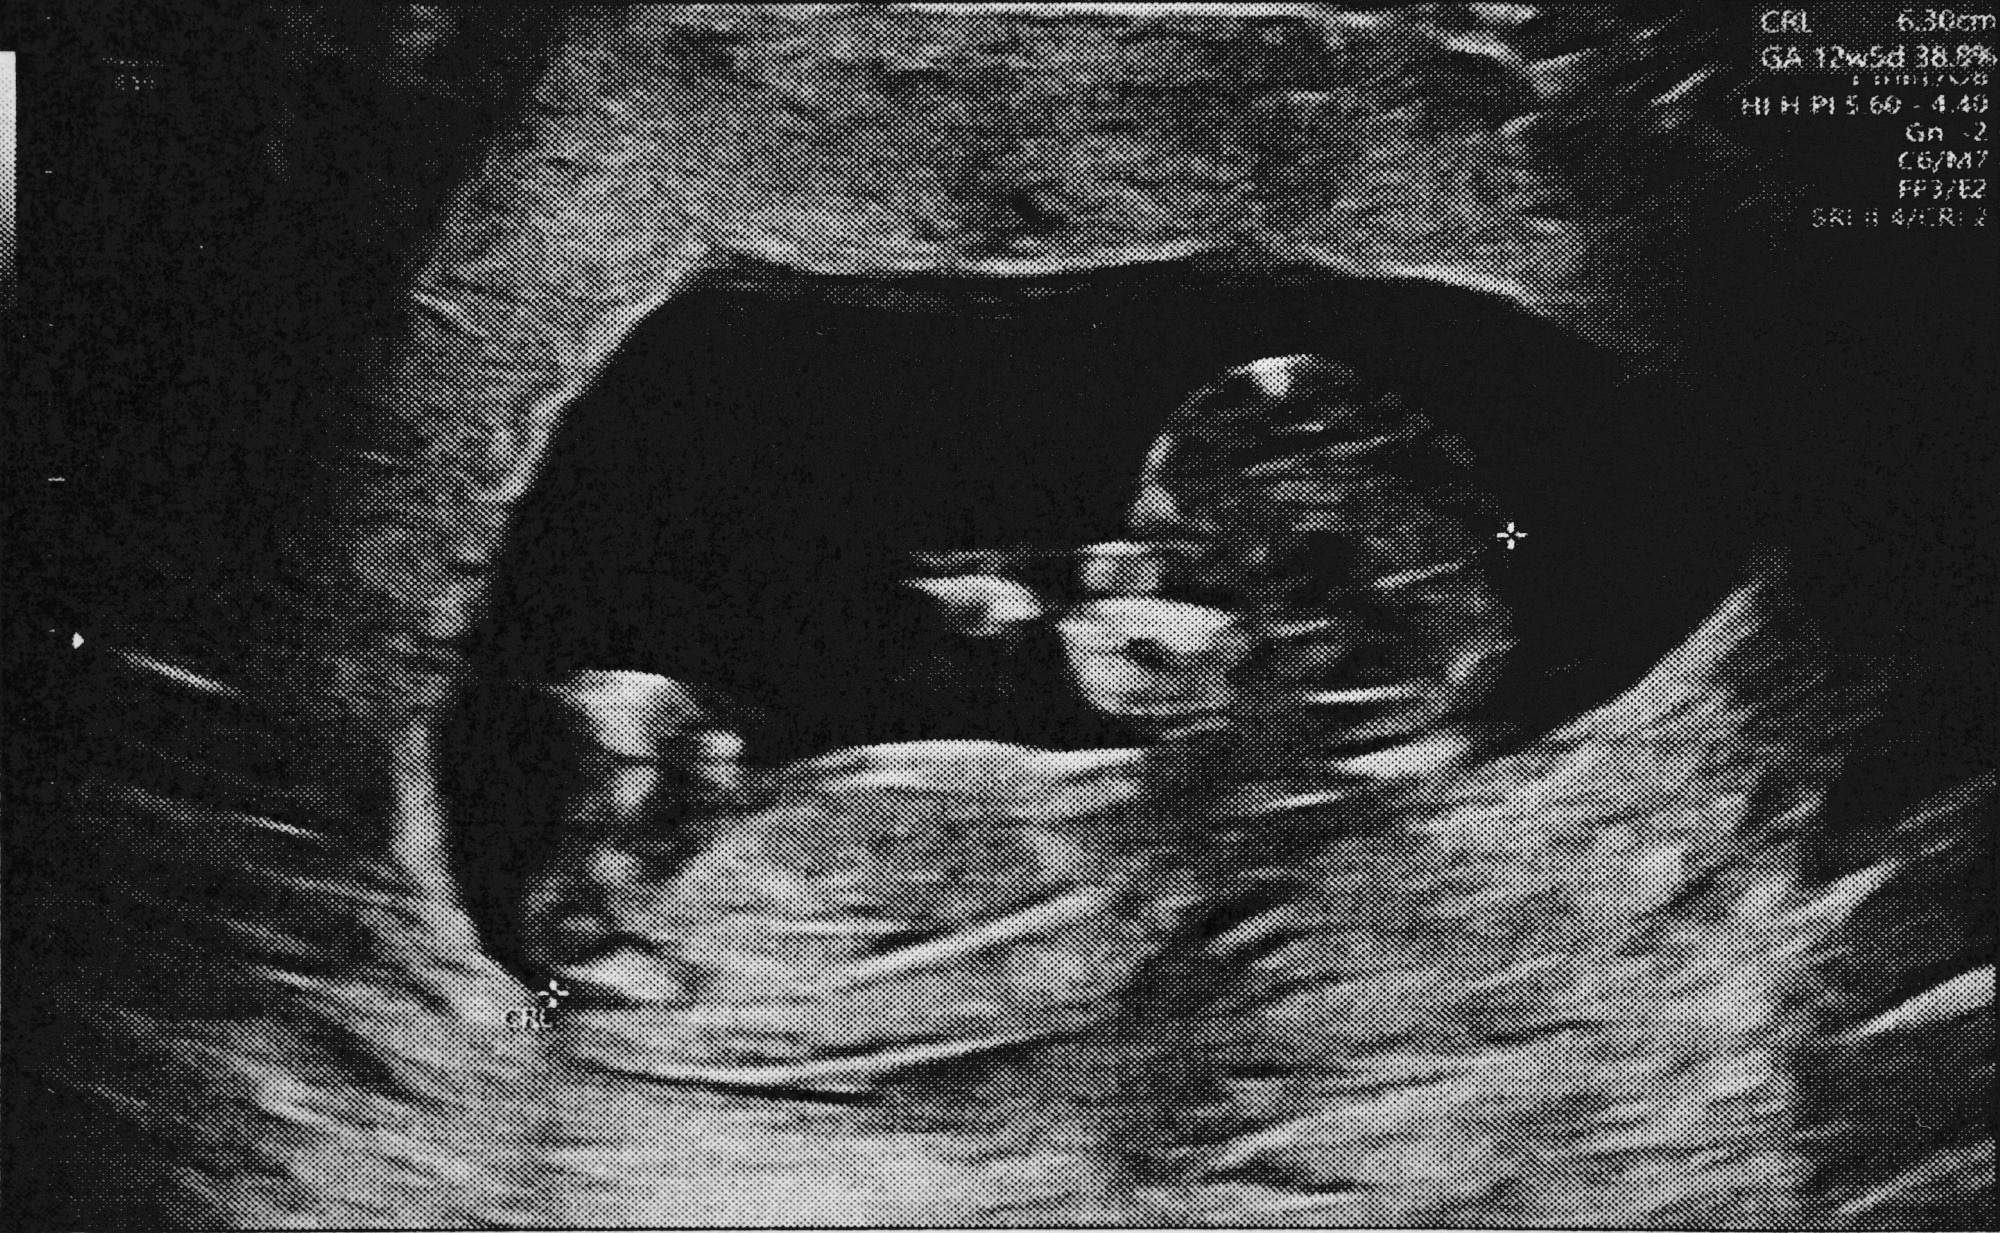

Fetal ultrasound imaging is crucial for observing fetal anatomy and the presence of any malformations. Considering the high rate of congenital anomalies of the kidneys and urinary tract (CAKUT) at one in 500 live births, the incorporation of DL into prenatal screening could allow clinicians to diagnose these conditions earlier to improve patient outcomes.

About 970 ultrasound images were used to train the current study, which consisted of about 650 controls and 320 images of anomalous kidney anatomy. More specifically, about 260 images exhibited unilateral dilation of the urinary tract (UTD), whereas 64 were images of unilateral multicystic dysplastic kidney (MCDK).